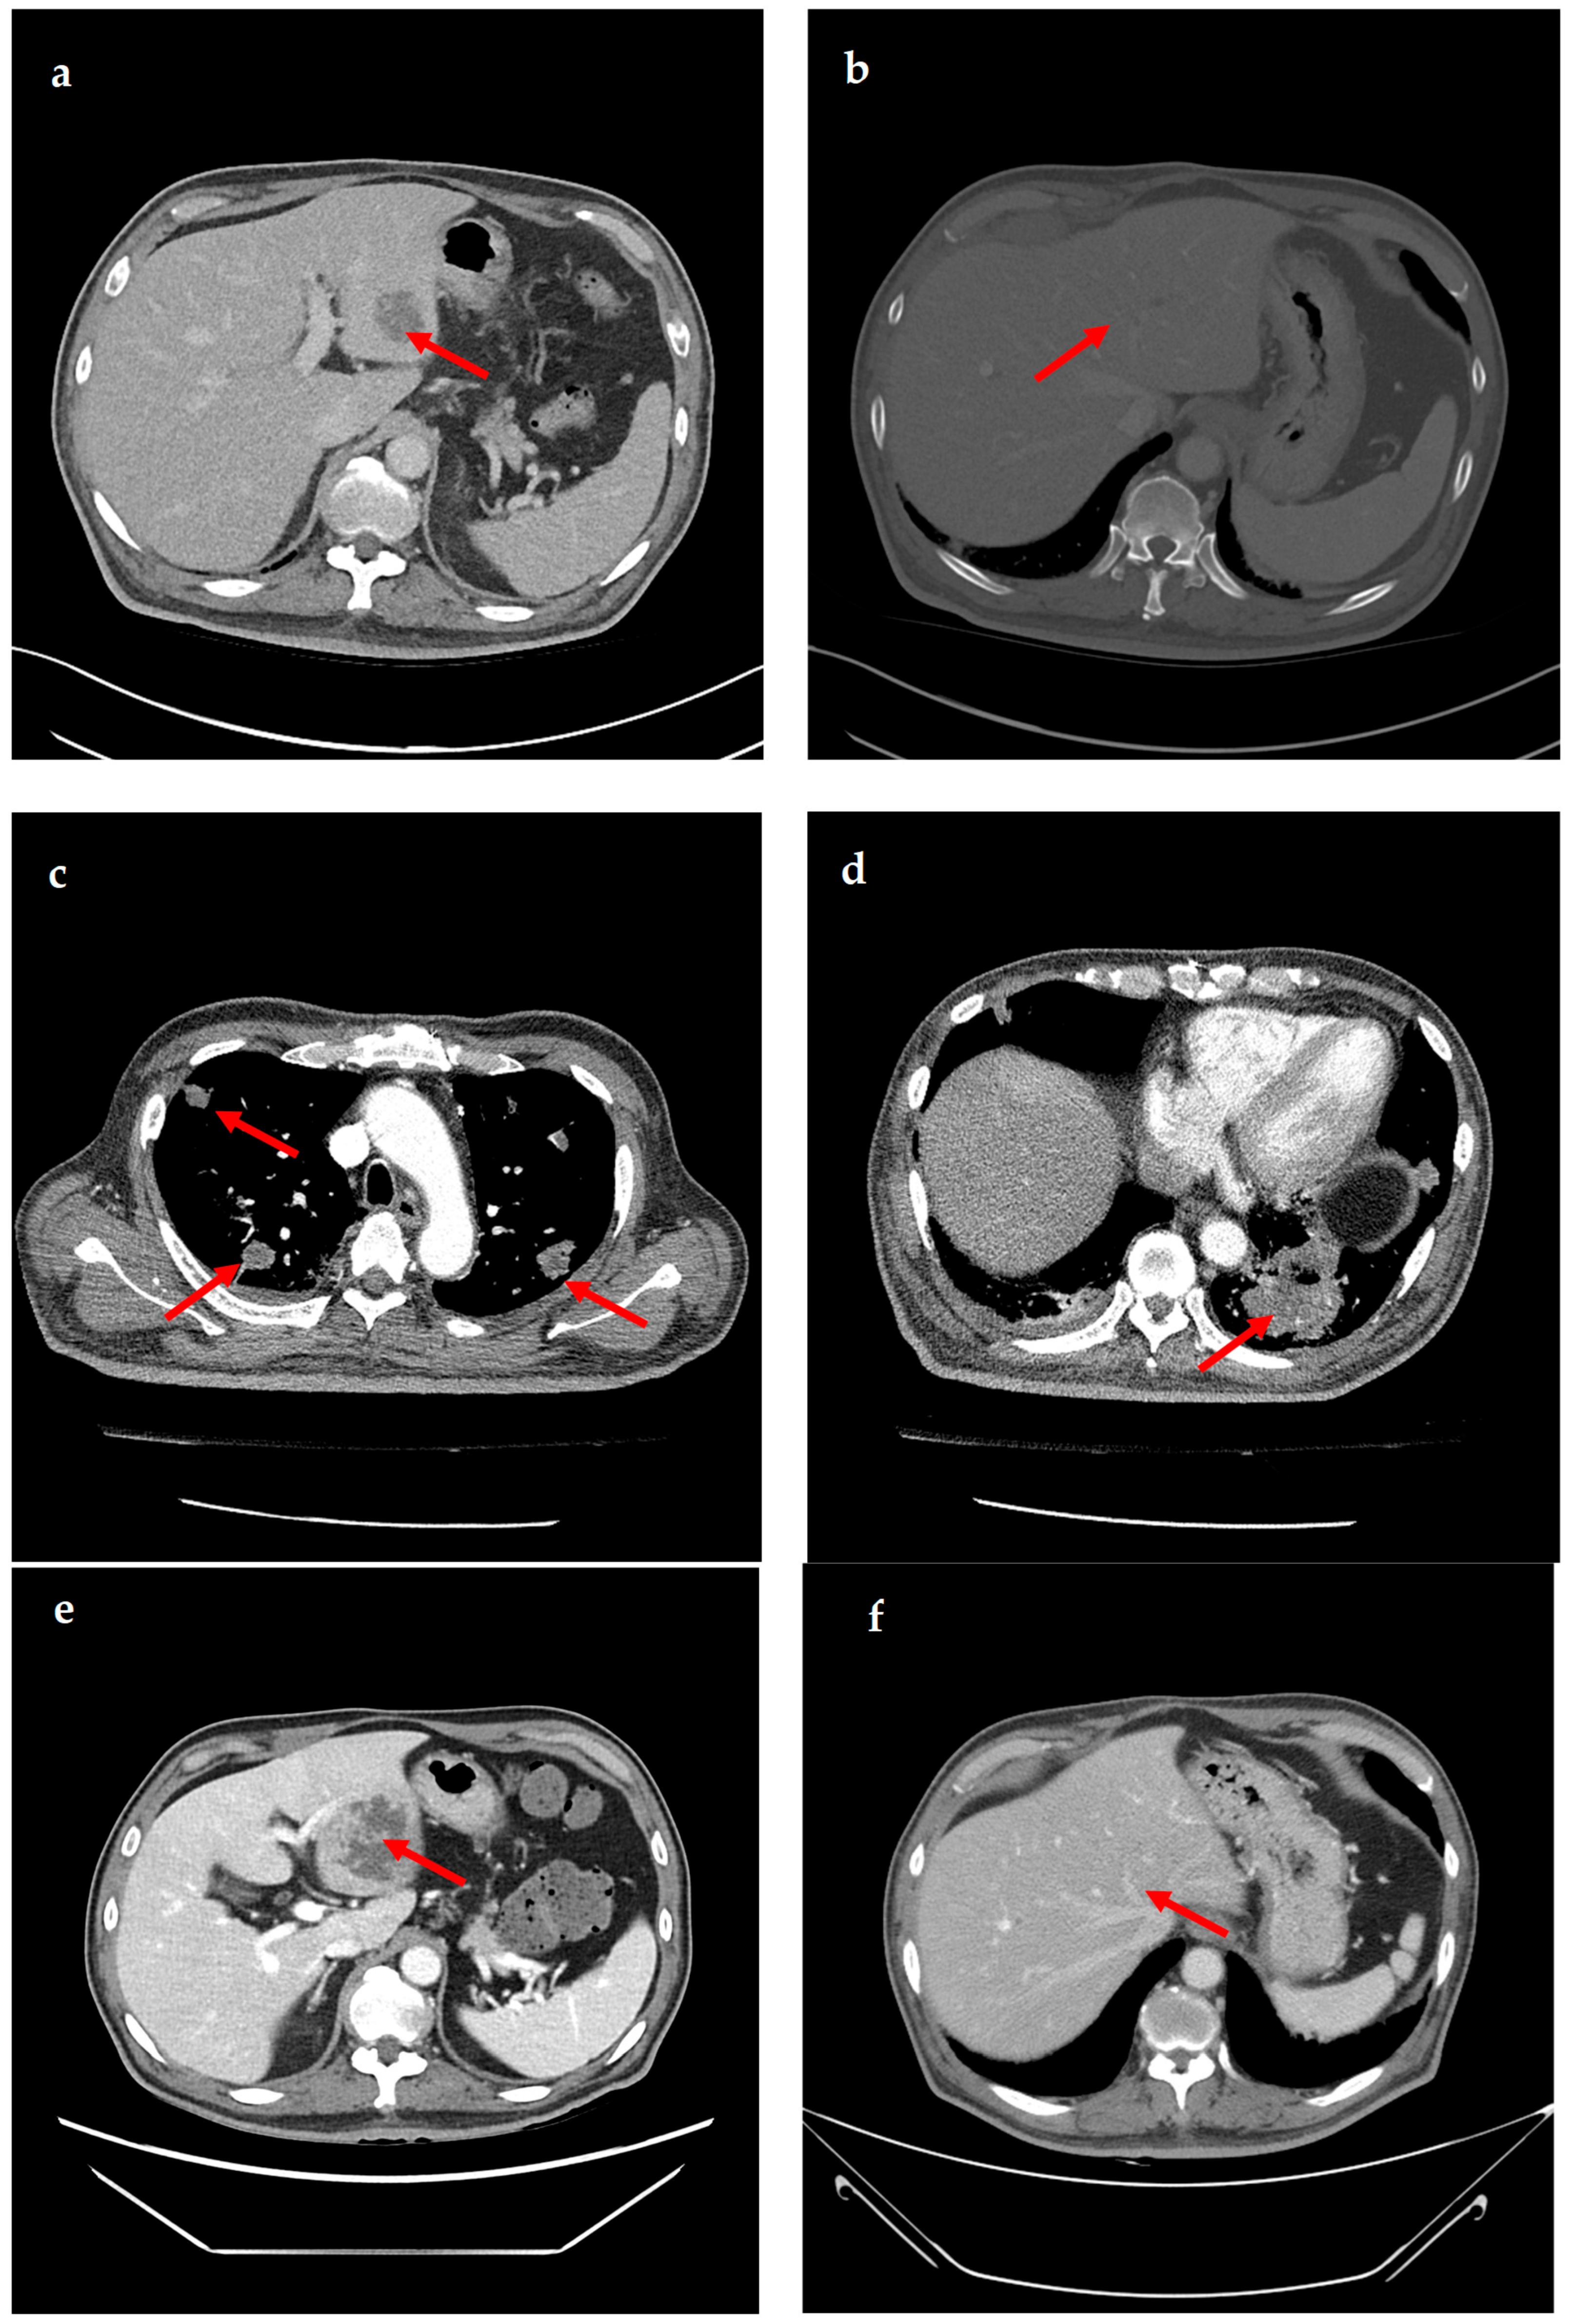

A 69-year-old male patient presenting with severe toothache 10 days before admission and melena 3 days before admission was admitted to the Infectious Disease Department of Kyung Hee University Hospital in the Republic of Korea in March 2025. The patient reported worsening toothache in the right upper gingiva with right facial swelling that began 5 days after a dental implant surgery at the upper right first premolar. Subsequently, the patient underwent incision and drainage at a local dental clinic one day before admission because of periodontitis that had spread to the facial area, as confirmed through the patient’s medical history. The patient had diabetes and was taking hypoglycemic agents. He had undergone coronary artery bypass grafting (CABG) for myocardial infarction 13 years previously. Additionally, he had undergone a prostatectomy for prostate cancer 2 years ago. He had been continuously taking clopidogrel (an antiplatelet agent) since undergoing CABG. The right buccal area of the face was swollen. Dental examination revealed a space abscess around the upper right first premolar (Figure 1). Panoramic dental X-ray showed that the implant fixture was placed in the alveolar bone of the upper right first premolar, and the external part has been removed (Figure 2). The implant fixture at the upper right first premolar was removed and irrigation and drainage were performed at the upper right first premolar and the vestibular area of the upper right second incisor, canine, and first premolar. The initial vital signs were blood pressure, 124/73 mmHg; pulse rate, 87 beats/min; respiratory rate, 20 breaths/min; temperature, 36.5 °C, oxygen saturation level, 98% on room air. Laboratory examination revealed a white blood cell (WBC) count of 6.23 × 109/L (83.0% neutrophils) and a C-reactive protein (CRP) level of 417.0 nmol/L. The aspartate aminotransferase, alanine aminotransferase, and alkaline phosphatase levels were 46, 57, and 97 IU/L, respectively. The serum creatinine level was 1.08 mg/dL and the BUN was 40 mg/dL. The serum sodium level was 129 mEq/L. Plasma level of glycated hemoglobin was 13.5%. Chest computed tomography revealed a mass-like lesion in the left lung with multiple small nodules in both lungs. Two sets of blood cultures were performed on the day of admission using BD Bactec Plus Aerobic/F and BD Bactec Plus Anaerobic/F bottles and a Bactec FX Instrument (Becton Dickinson, Sparks, MD, USA). The patient underwent esophagogastroscopy, which revealed active bleeding from multiple duodenal ulcers and subsequently received hemostatic treatment. A gastrointestinal bleeding dynamic computed tomography (CT) scan showed a liver abscess at S2/3 (3.1 cm) (Figure 3a) with focal septic thromboembolism in the left hepatic vein (Figure 3b). Chest CT revealed mass-like consolidation and air densities in the left upper and lower lobes, along with multiple irregular nodules with ground-glass opacities in both lungs (Figure 3c,d).

Figure 3. Computed tomography (CT) images showing liver abscess and septic pneumonia. (a) Gastrointestinal bleeding dynamic CT images show liver abscess (approximately 3.1 cm) at segments 2/3. (b) Gastrointestinal bleeding dynamic CT images show focal septic thromboembolism in the left hepatic vein. (c,d) Chest CT images show multiple mass-like consolidations in both lungs. (e) Abdominopelvic CT images show an increased liver abscess (approximately 6.9 cm) at segments 2/3. (f) Abdominopelvic CT images show that the liver abscess has resolved.

The patient was empirically prescribed intravenous piperacillin-tazobactam (13.5 g/day). On the 4th day of hospitalization, K. pneumoniae was identified in two blood cultures. K. pneumoniae was susceptible to cefotaxime (minimal inhibitory concentration [MIC] ≤ 1 µg/mL), ceftazidime (MIC ≤ 1 µg/mL), piperacillin–tazobactam (MIC ≤ 8 µg/mL), and meropenem (MIC ≤ 1 µg/mL), but not ampicillin (MIC > 16 µg/mL). K. pneumoniae was also identified in the sputum culture. The patient underwent daily gingival irrigation. An ophthalmic examination revealed no signs of endophthalmitis. The patient did not have fever from the 8th day of hospitalization. It was initially switched to meropenem (3 g/day) due to the patient’s critical condition and administered for 6 days. Once the patient stabilized, the antibiotic treatment was switched to ceftriaxone (2 g/day) and administered for 4 days. On the 14th day of hospitalization, follow-up CT showed that the size of the liver abscess had significantly increased from 3 cm to 6.9 cm (Figure 3e). Drainage of the liver abscess was considered; however, the patient refused, and because the abscess was approximately 3 cm in size, only antibiotic treatment was maintained. On the 15th day of hospitalization, the patient was discharged at his request, and treatment was continued on an outpatient basis. The patient was administered ciprofloxacin (1000 mg/day) for approximately 5 months after discharge. One month after admission, the WBC count and CRP level returned to within reference ranges. Four months after discharge, follow-up CT showed that the liver abscess and septic pneumonia had resolved (Figure 3f). The clinical course and antibiotic treatment of a case patient are shown in Figure 4.